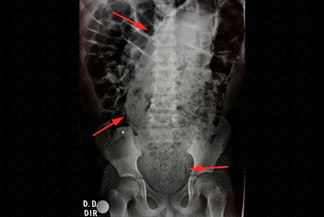

Texto alternativo para a imagem Figura 1. Créditos: Dra. Elazir Mota - Rio de Janeiro/RJ.

Descrição da figura 1: Radiografia de abdome AP de paciente infantil com aganglionose intestinal (megacólon), evidenciando importante distensão do reto e sigmoide por conteúdo fecal (fecaloma), como indicam as setas vermelhas.

Fecaloma: Grande quantidade de fezes, na maioria das vezes presente no reto e sigmoide. Dependendo do conteúdo fecal impactado, pode haver importante distensão das alças intestinais a montante, simulando um quadro de obstrução intestinal.

• Radiografia de abdome: Conteúdo moteado na ampola retal que se encontra distendida, podendo haver distensão a montante ou não;